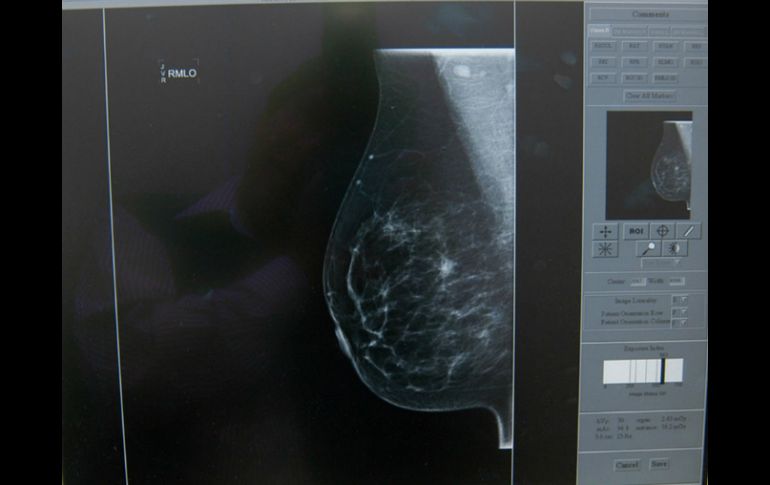

Suplementos | La mayoría de los cánceres de mama que se expanden por el cuerpo terminan en los huesos Proteger los huesos evitaría metástasis del cáncer de mama Alrededor del 85 por ciento de los cánceres de mama que se expanden por el cuerpo terminan en los huesos Por: NTX 28 de mayo de 2015 - 13:53 hs Es necesario llevar a cabo más estudios para establecer exactamente cómo es que interactúan las células óseas y las enzimas LOX. EL INFORMADOR / ARCHIVO LONDRES, INGLATERRA (28/MAY/2015).- Ciertos tipos de cáncer de mama pueden manipular la estructura de los huesos para hacerles más fácil multiplicarse y expandirse, según un nuevo estudio realizado por investigadores de la Universidad de Sheffield, Inglaterra. El descubrimiento podría conducir a tratamientos destinados a prevenir o frenar la propagación del cáncer de mama con una efectiva protección de los huesos, donde las células cancerígenas parecen "fertilizarse". Alrededor del 85 por ciento de los cánceres de mama que se expanden por el cuerpo terminan en los huesos, punto en el cual son difíciles de tratar y más mortales. Sin embargo, medicamentos baratos que se utilizan para tratar la osteoporosis podrían salvar miles de vidas cada año ya que ayudarían a "detener el cáncer de mama en su camino, protegiendo los huesos de la influencia nefasta de un tumor", sugieren los científicos. Los especialistas identificaron una enzima llamada LOX, producida por el tumor primario en la mama y que se libera en la sangre, la cual es responsable su propagación a los huesos, causando la mayoría de las muertes por este tipo de cáncer. La enzima forma agujeros en los huesos, proporcionando un terreno fértil para el crecimiento de las células cancerígenas, que finalmente hacen metástasis, explican los científicos que llevaron a cabo una serie de experimentos con ratones. Este proceso podría ser interrumpido con bisfosfonatos que previenen la pérdida ósea y se utilizan para tratar la osteoporosis, ya que fueron capaces de evitar cambios en los huesos y con ello bloquearon la propagación del cáncer. "Creemos que es un avance significativo para tratar de evitar la metástasis en el cáncer de mama", asegura la doctora Alison Gartland, de Biología del Cáncer en la Universidad de Sheffield. Los investigadores afirman que es necesario llevar a cabo más estudios para establecer exactamente cómo es que interactúan las células óseas y las enzimas LOX para desarrollar tratamientos eficaces para impedir la metástasis. Temas Cáncer Cáncer de mama Enfermedades Calor de hogar Lee También Jalisco refuerza lucha contra el cáncer de mama Dos batallas contra el cáncer de mama Cáncer de mama: “Nadie te prepara para esto” El peligroso avance del cáncer de colon en México Recibe las últimas noticias en tu e-mail Todo lo que necesitas saber para comenzar tu día Registrarse implica aceptar los Términos y Condiciones